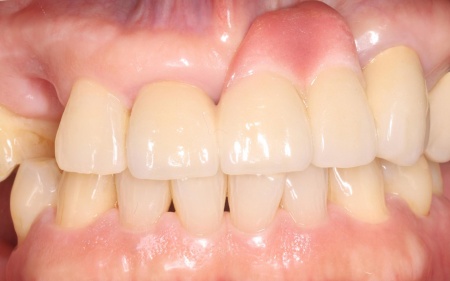

| 主訴 | 当院で左下の一番奥の歯にインプラント治療(歯を失った部分に人工歯根を埋め込み歯を補う治療)を行った患者様です。 インプラントの手前にある銀歯の見た目が気になるとのことで、「銀歯をやり直したい」とご相談いただきました。 |

| 診断 | 拝見したところ、インプラントの手前の歯には保険の金属製の被せ物(銀歯)が装着されていました。 しかし、被せ物と歯の間にわずかな隙間や段差が生じており、ぴったりと合っていない状態でした。 このような隙間には、食べかすなどの汚れや虫歯や歯周病の原因となる細菌の塊「プラーク」が蓄積しやすくなります。 レントゲンを撮り確認したところ、現時点では歯の神経や根の状態に異常は認められなかったものの、このまま放置すると、被せ物の隙間からプラークの蓄積が進み虫歯や歯周病になる恐れがあります。 以上のことから、患者様のご希望も踏まえ被せ物のやり直しが必要と診断しました。 |

| 行ったご提案・治療内容 | 患者様は「強度があって見た目もいいものがいい」と希望されており、被せ物にはセラミック素材の一種であるオールジルコニアクラウンを提案し、同意いただきました。

ジルコニアは天然歯に近い白さと自然な質感を再現できるうえ、強度が高いため奥歯のように噛む力がかかる部位にも適した素材です。 まず、既存の銀歯を丁寧に除去します。 なお、治療後に患者様より「もう1本手前の銀歯もやり直したい」とのご希望があり、後日こちらも被せ物をやり直す予定です。 |

治療後